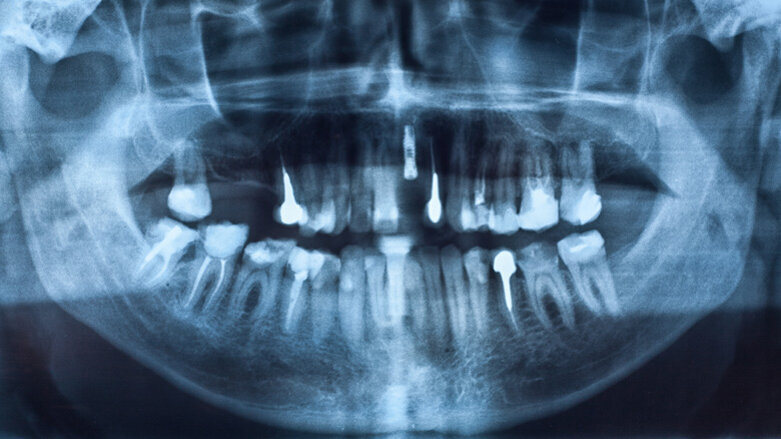

An der Untersuchung, die im Journal of Oral Implantology erschienen ist, nahmen 25 Frauen über 60 Jahre mit einer Osteoporose-Diagnose teil, die kurz zuvor ein Implantat erhalten hatten. Elf der untersuchten Frauen nahmen aufgrund ihrer Osteoporose Bisphosphonate ein. Insgesamt wurden bei den elf Frauen 25 Implantate gesetzt, wovon drei innerhalb eines Jahres nach der Implantation verloren gingen. Die restlichen 14 Frauen nahmen keine Bisphosphonate ein, bei ihnen verlief die Osseointegration der Implantate komplikationslos.

Bisphosphonate sind bei Osteoporose in der Regel das Mittel der Wahl, da sie den Knochenabbau im Körper bremsen. Zum Umgang mit Patienten, die diese Medikamente einnehmen und vor einer geplanten Implantation stehen, hat die DGMKG eine S3-Leitlinie erarbeitet.